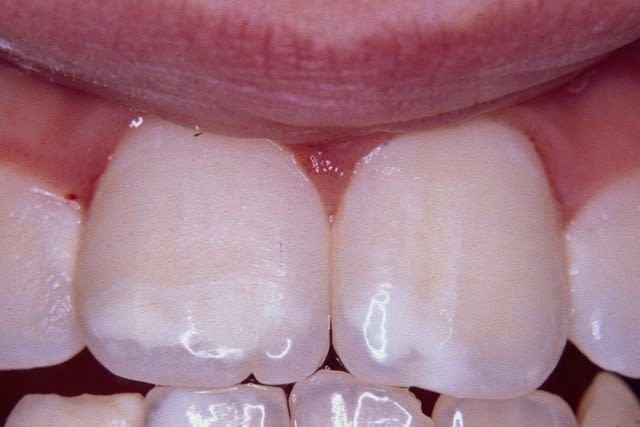

Bonjour,

Je finalise ma thèse sur la MIH (Hypominéralisation Molaire-Incisive). Je n'ai que des photos assez médiocres... Je vois que certains d'entre vous sont très doués en photo et c'est une pathologie très courante (10-15%) : si quelqu'un a quelques clichés à m'envoyer, je lui en serai très reconnaissant. Bien sûr, son nom serait cité en référence.

PS : en pièce jointe, le mieux que j'arrive à faire, pas super...

Pour les MIH :

- Opacités délimités, contours nets

- Couleur blanc-jaune à brun, "crème" en général

- Forme des taches

- Affecte au moins une première molaire permanente et dans 75% des cas une ou plusieurs incisives permanentes. Très rarement d'autres dents (pointes canines ou secondes molaires)

- Atteintes asymétriques (on peut voir une 16 très atteinte, une 36 modérément atteinte, une 26 intacte)

1ère photo : fluorose légère

2ème : MIH